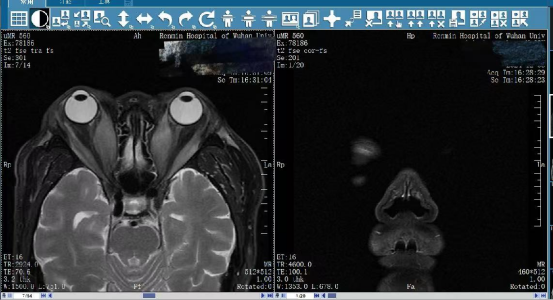

张先生来到武汉大学人民医院就诊,眼科中心武犁副教授接诊后,通过视力、视野、眼底、角膜情况、眼眶三维 CT 及 MRI 等精准检查,发现患者双眼视神经严重受压,确诊为「甲状腺功能障碍性视神经病变(DON)」——这是甲状腺相关眼病最凶险的类型,不及时干预将导致永久性失明。

术后,张先生原本被挤压变形的视神经已恢复自然形态,视网膜出血灶明显吸收。术后三天即可实现自主闭眼,解除了角膜溃疡等风险。